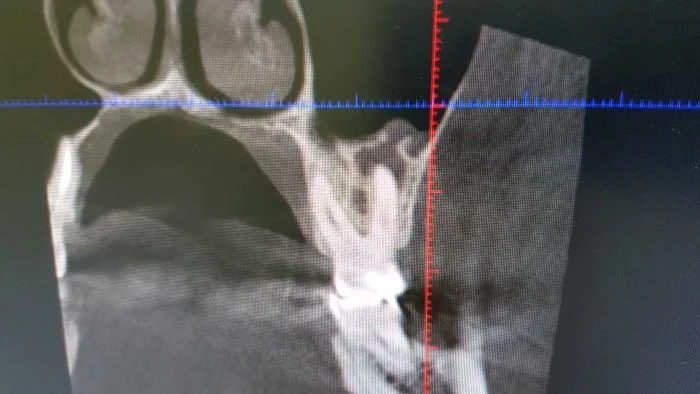

Вовремя непролеченая киста на зубах верхней челюсти может прорвать мембрану гайморовой пазухи и вызвать одонтогенный гайморит. Который не вылечить не удалив зуб. В этом случае стоматологи работают совместно с отоларингологами. Однако здесь уникальность ситуации в том, что снимок сделан когда киста уже прорвала пазуху, но гайморит еще не начался. Сейчас с пациенткой работает стоматолог-терапевт и пытается спасти зуб. Пациентке повезло, обычно пациенты приходят уже с гайморитом.